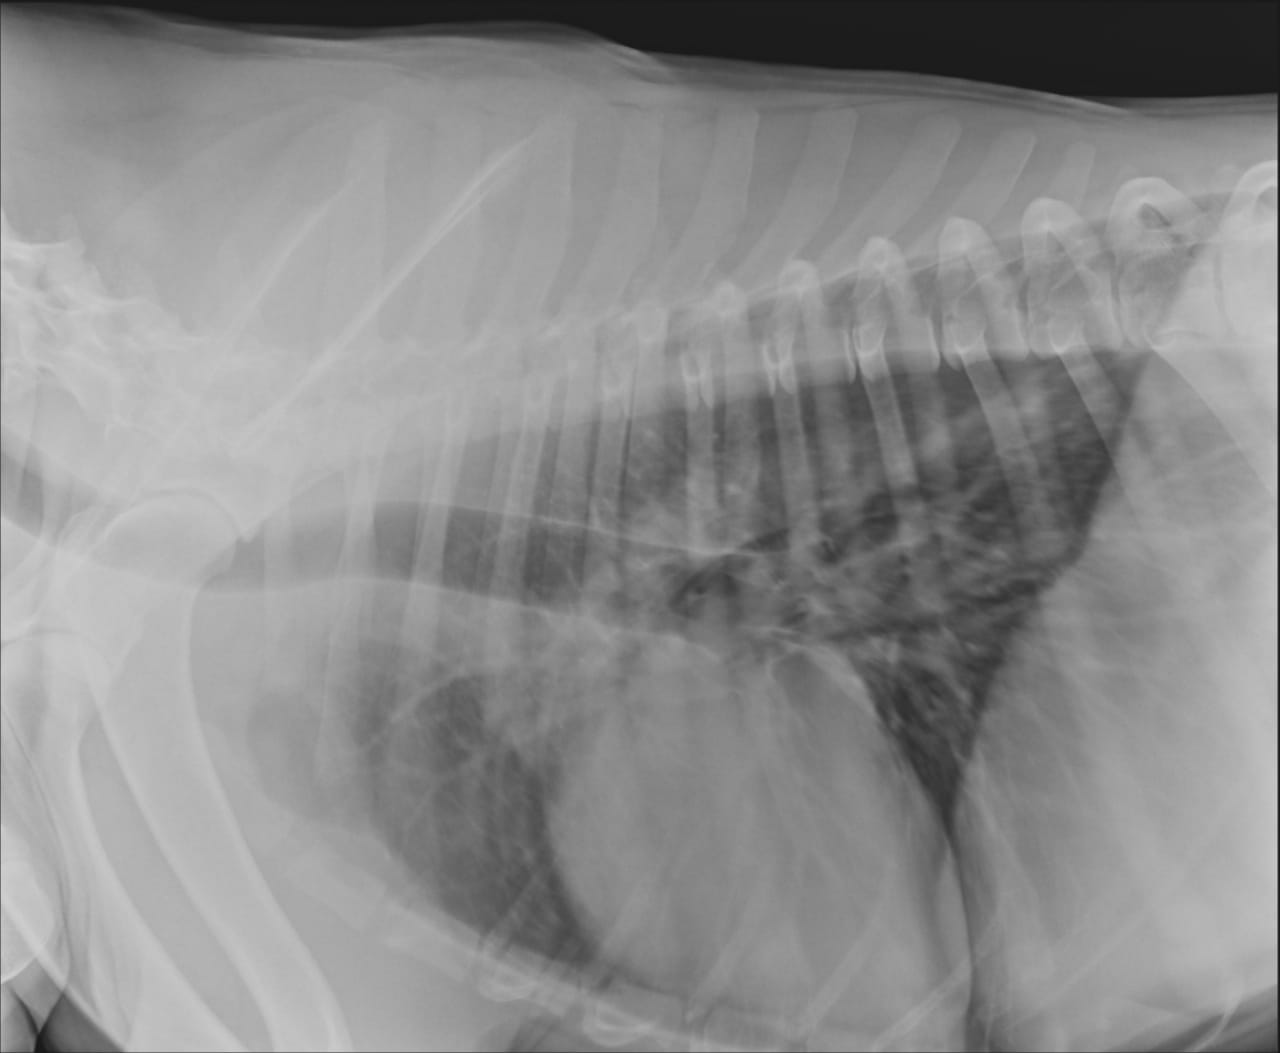

Анализы Арчи. Сердца и легких

Сегодня Арчуна Ирина возила на рентген легких и сдали анализ мочи. Результат анализа мочи готов будет завтра. Рентген легких выставляю.

Ирина, ждем твоего вердикта по рентгена и можно ли нам готовить Арчи к операции по глазам.

Антибиотика курс пропили.

Лучше чем было, но явно не норма:(